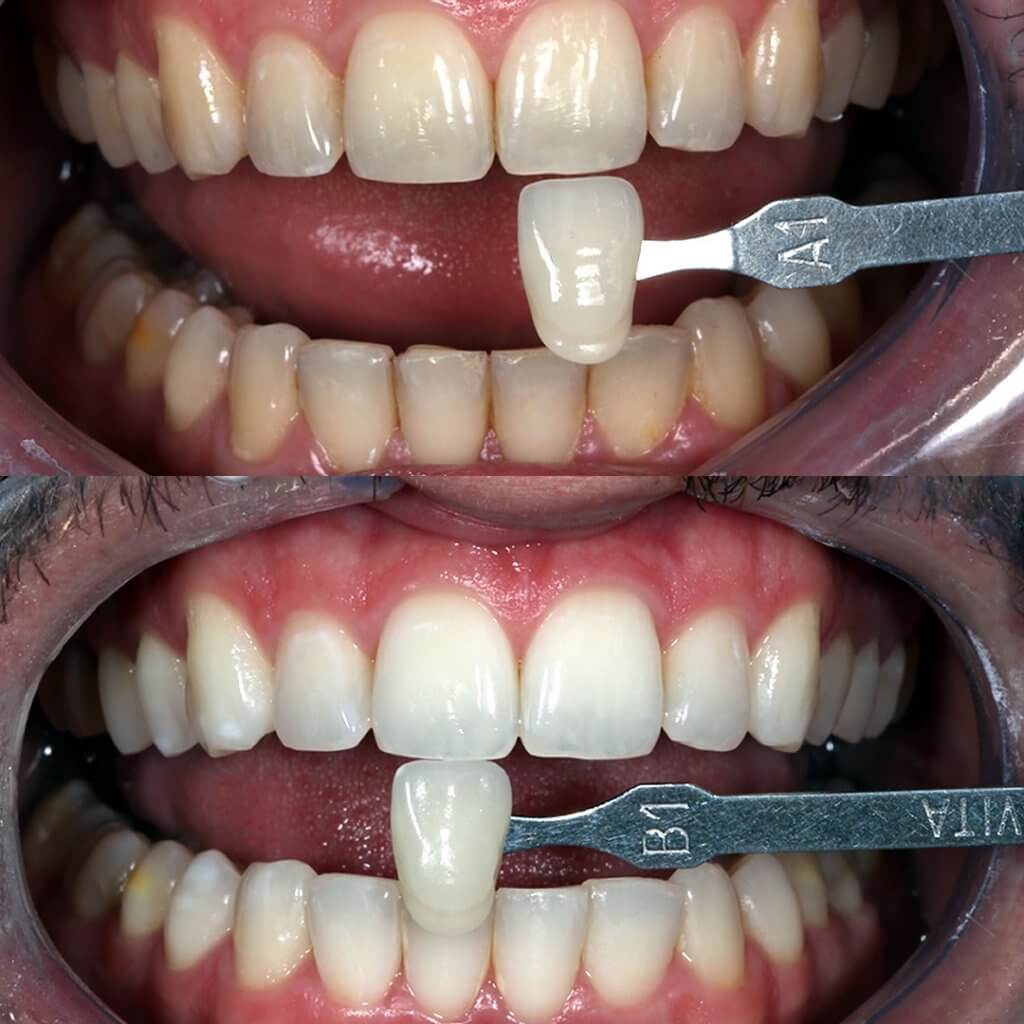

Clareamento Dental

O claramento dental é realizado com a aplicação de substâncias clareadoras, que melhoram a cor dos dentes (clareiam), melhorando a estética. Em alguns casos o clareamento também consegue remover pequenas manchas.

Existem duas formas básicas para realização do clareamento dental, uma em que o paciente aplica os géis clareadores, em casa, supervisionado pelo dentista e outra em que o tratamento é todo realizado em consultório.